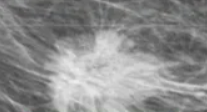

Q

La imagen muestra un carcinoma medular, que marcadores esperarías encontrar:

A

Triple Negativo

* RE, RP, HER2 (-)

* BCRA1+

* mas mucho infiltrado linf.